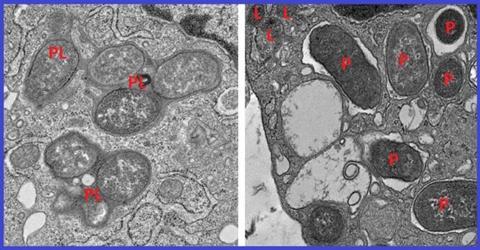

Using a powerful machine learning tool, the researchers analyzed thousands of macrophage gene expression patterns from colon tissue affected by IBD and from healthy colon tissue. They identified a macrophage gene signature consisting of 53 genes that reliably separates reactive, inflammatory macrophages from tissue-healing macrophages.

One of these 53 genes encodes a protein called girdin. Further analysis revealed that in non-inflammatory macrophages, a specific region of the NOD2 protein binds to girdin. This suppresses runaway inflammation, clears harmful microbes and allows for the repair of tissues damaged by IBD. But the most common Crohn’s disease mutation to the NOD2 gene deletes the section of the gene that girdin would normally bind to. This results in a dangerous imbalance between inflammatory and non-inflammatory macrophages.